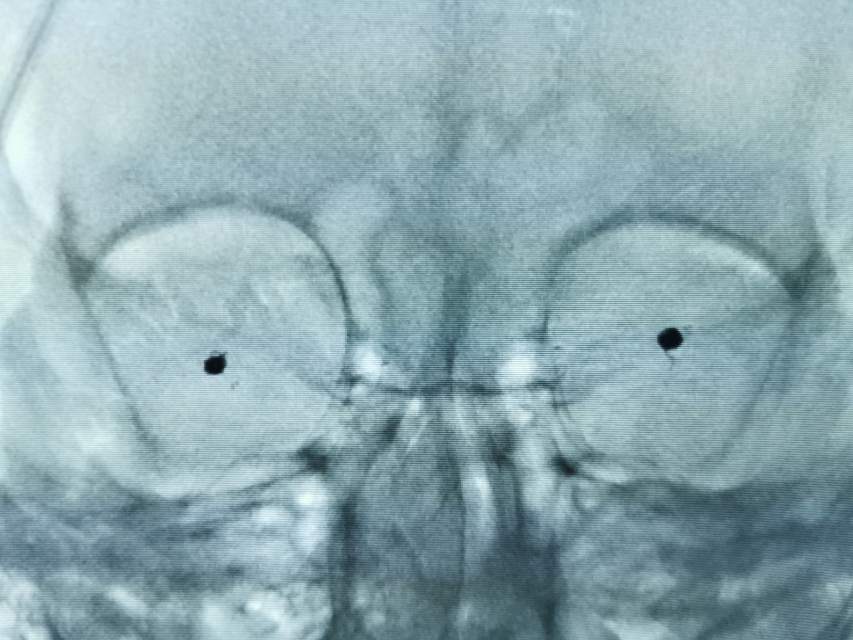

患者大年初一颅内动脉瘤破裂,查出多发颅内动脉瘤,大年初一栓塞破裂的大脑中—豆纹动脉动脉瘤,另外一个对侧的大脑中动脉分叉部动脉瘤形态不规则,顶端有明显的小泡,存在随时破裂的高风险,决定给予支架辅助栓塞术